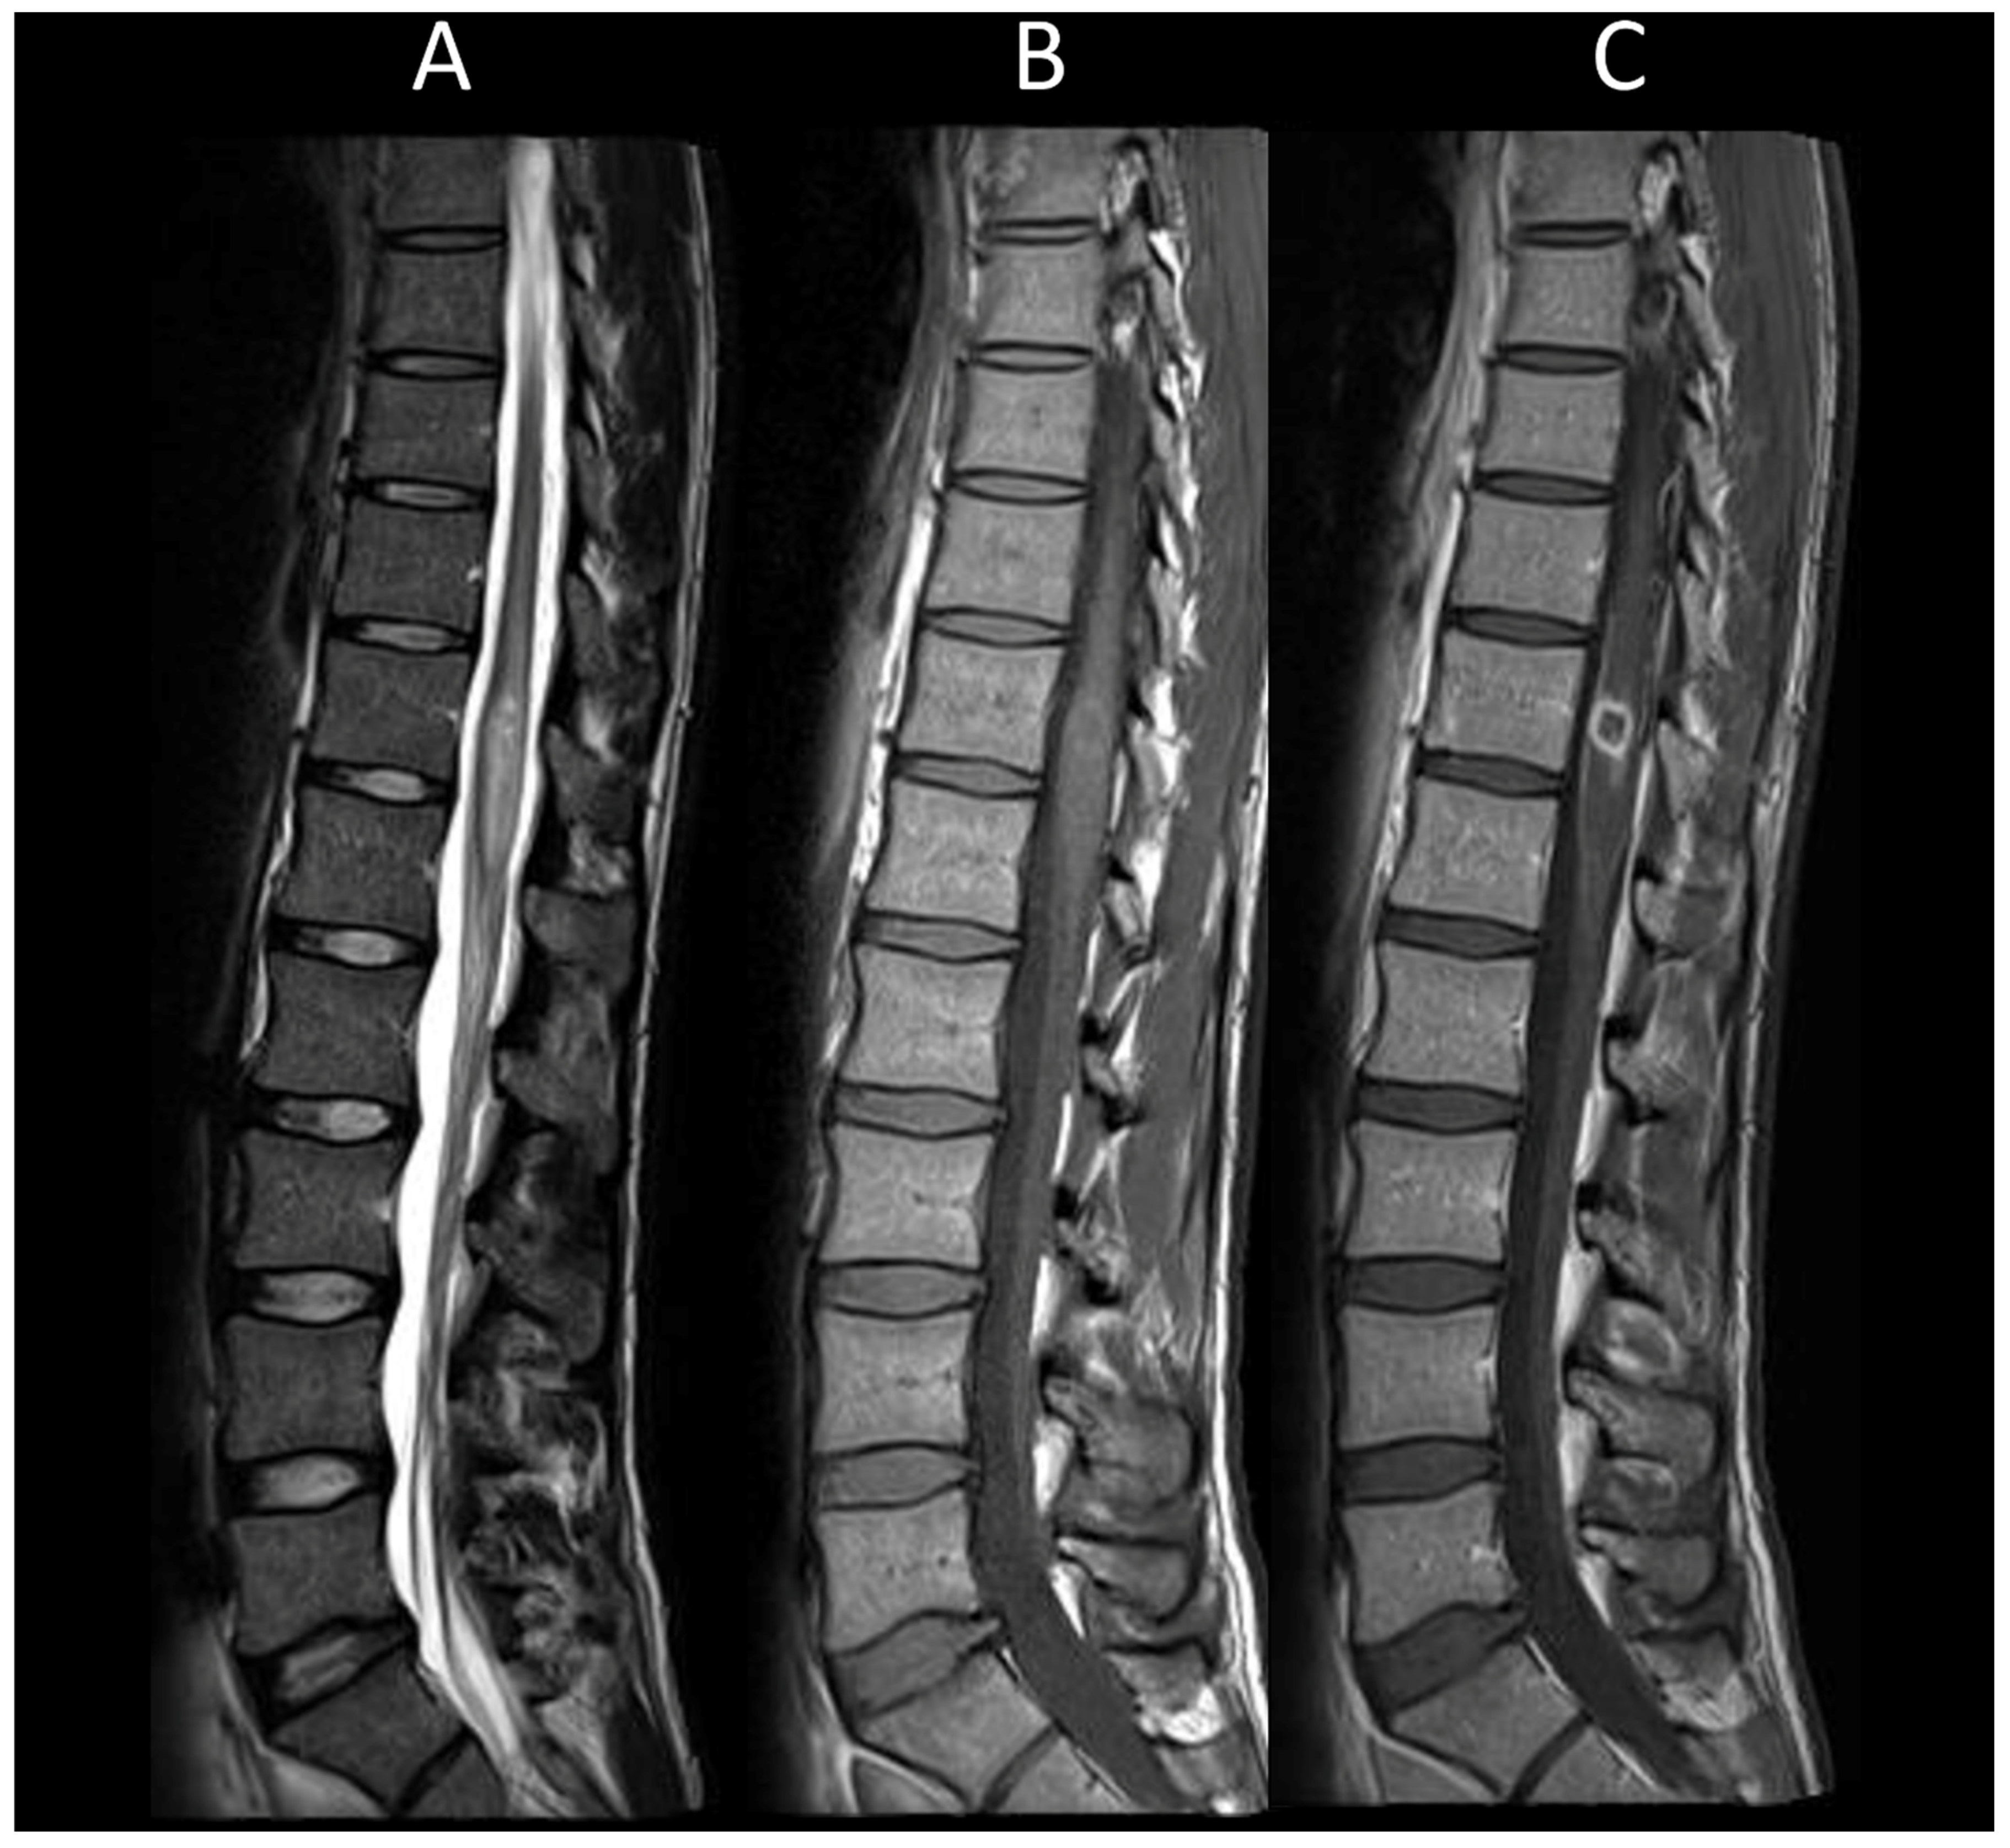

3.2. Degenerative Compressive Myelopathy

3.3. Vascular Myelopathies